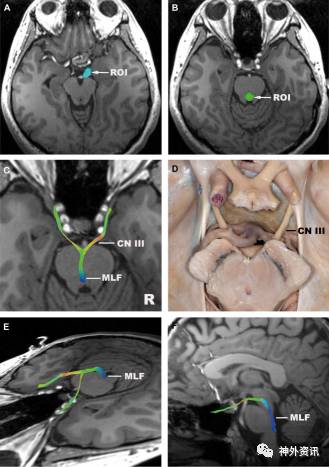

图4. 动眼神经。A.ROI置于脑池段;B.ROI置于桥脑上端水平四脑室前部;C.动眼神经(轴向位),纤维束从脚间池进入脑干,然后近脑干中线处下降;D.对应的解剖示意图;E.动眼神经(斜位);F.动眼神经(矢状位)。MLF:内侧纵束。